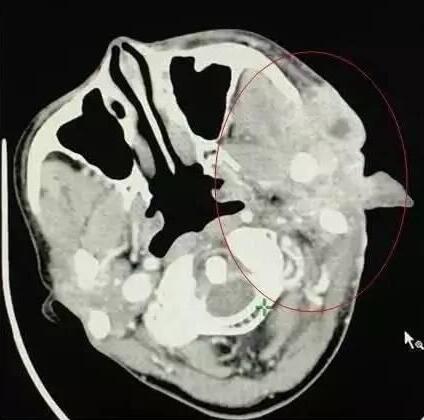

腮腺癌

患者女性,63岁。

A45治疗前

A45治疗一个疗程后,病灶缩小非常明显,皮肤逐渐愈合好转。